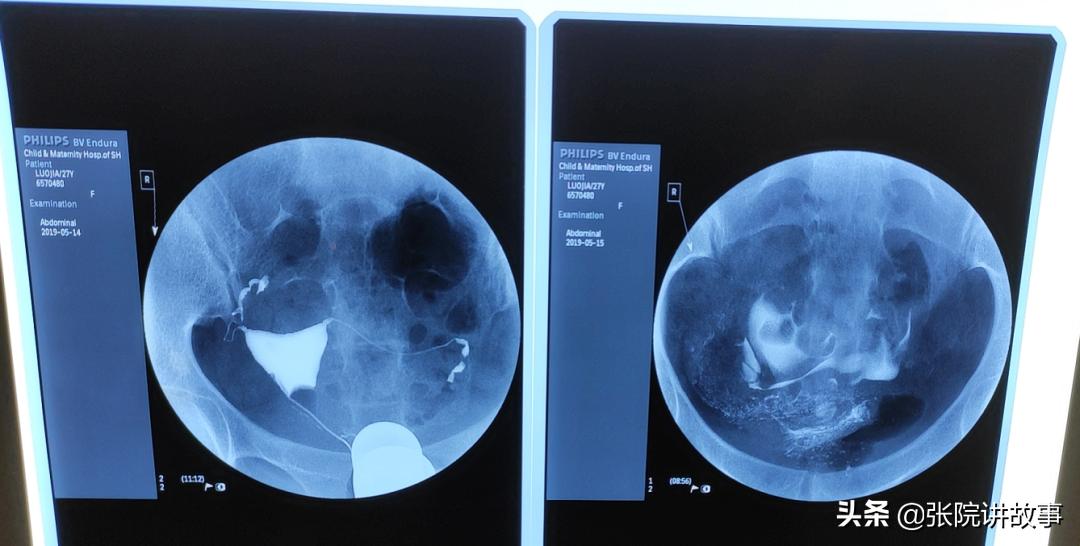

我们再回到这对小夫妻身上,从女孩的造影片子,可以看到造影剂通过两侧输卵管流入盆腔,但右侧输卵管走形不是很好,远端被牵拉上举,弥散片也看到造影剂堆积残留,所以影响到卵子捕获。接下来的时间,两人都非常配合我们的诊疗措施,坚持中西医结合治疗和盆底的物理治疗,有针对性的治疗之后,第一次人工授精就怀孕了,两人欣喜若狂,庆幸自己如愿以偿。

女性的输卵管包括了伞部、壶腹部、峡部、间质部,子宫输卵管造影是评估输卵管功能的首选评估方式,不仅可以看到宫腔的形态,以及输卵管管腔内部的形态,还有管腔外围的走形,从而综合判断输卵管管腔的通畅程度以及全程走形状况。对于造影片子的解读,必须注重细节,要仔细观察造影剂通过的每一段输卵管时的显影情况。

对于输卵管内部的评判,也需要认真仔细观察它的显影是否完整。如果局部显影的缺失或者是狭窄,或者局部有增粗膨大,膨大部位的远端是否有粘连,这些都会造成造影剂不能够顺利的排出、堆积;还有一部分是局部积水的情况。所以造影的时候我们主张当造影剂进入到宫腔、进入到输卵管之后,还应该让患者在床上翻一个滚儿,再去拍片,只有这样在延迟片上才可以清楚的判断造影剂的弥散情况。